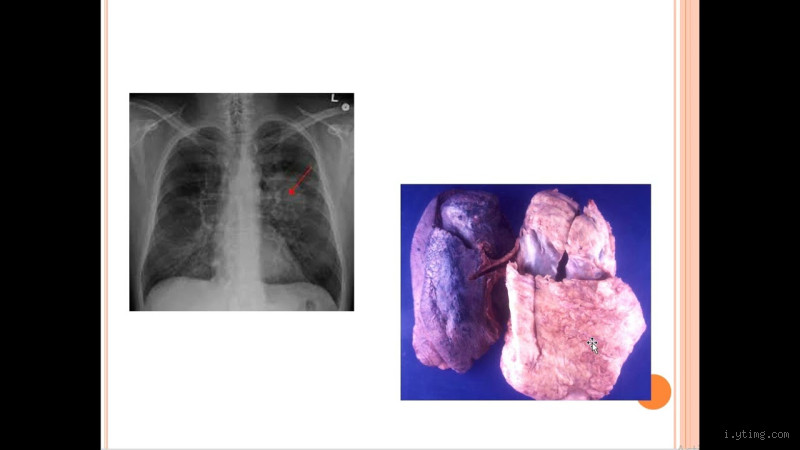

عندما يشتبه الطبيب في وجود كتلة خبيثة، فإنه يقوم عادة بإجراء مجموعة من الفحوصات. تشمل هذه الفحوصات الأشعة السينية، الفحص بالموجات فوق الصوتية، أو حتى الخزعة (أخذ عينة من الكتلة لفحصها تحت المجهر).